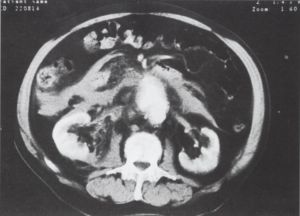

3. ábra.

Infrarenálisan kb. 7 cm átmérőjű aneurysma, az aorta meszes falú, jobb oldalon és dorsalisan sarló alakú hipodenz terület - fali thrombus. A retroperitoneumban magas denzitású képlet, haematoma.